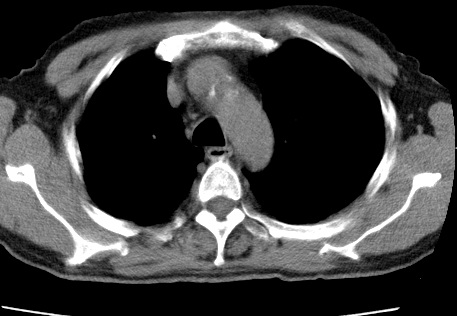

标题: CT24032:男65岁,咳嗽,吸烟20余年,无发热,咳痰 [打印本页]

标题: CT24032:男65岁,咳嗽,吸烟20余年,无发热,咳痰

考虑右肺中叶不张,请大家发表意见

右肺中叶不张、肺门轮廓增大,占位不除外;建议增强,必要时支气管镜详查。

右肺中叶支气管闭塞,中叶肺不张,右侧肺门见肿块影。中心型肺癌的可能大。建议支气管镜检查。

右中叶体积明显缩小,且其支气管未显示,先考虑:中心型肺癌班右中叶肺不张。

建议:支气管镜检查。

右肺门旁类圆形肿块影,右肺中叶不张,建议纤支镜检查。

1右肺门旁类圆形肿块影,右肺中叶不张,建议纤支镜检查

2右侧胸膜增厚,右侧叶间胸膜区钙化

3右肺下叶小囊状透亮影考虑肺气肿